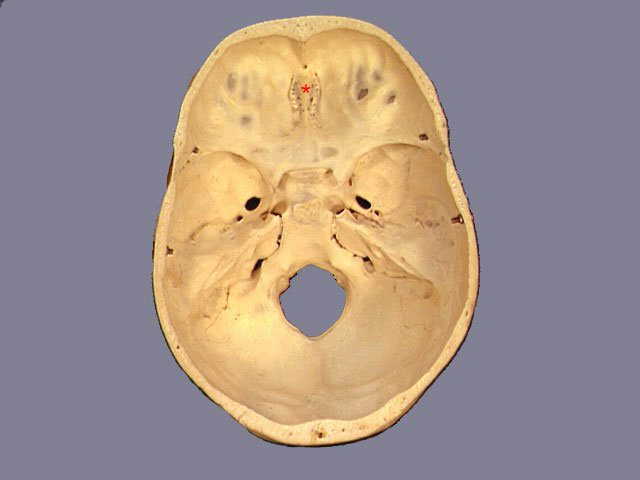

Identify the structure marked by the RED asterisk

Crista Galli